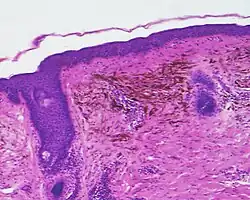

Histopathology

Micrograph of a blue nevus showing the characteristic pigmented melanocytes between bundles of collagen. H&E stain. Blue nevus

Blue nevus Cellular blue nevus